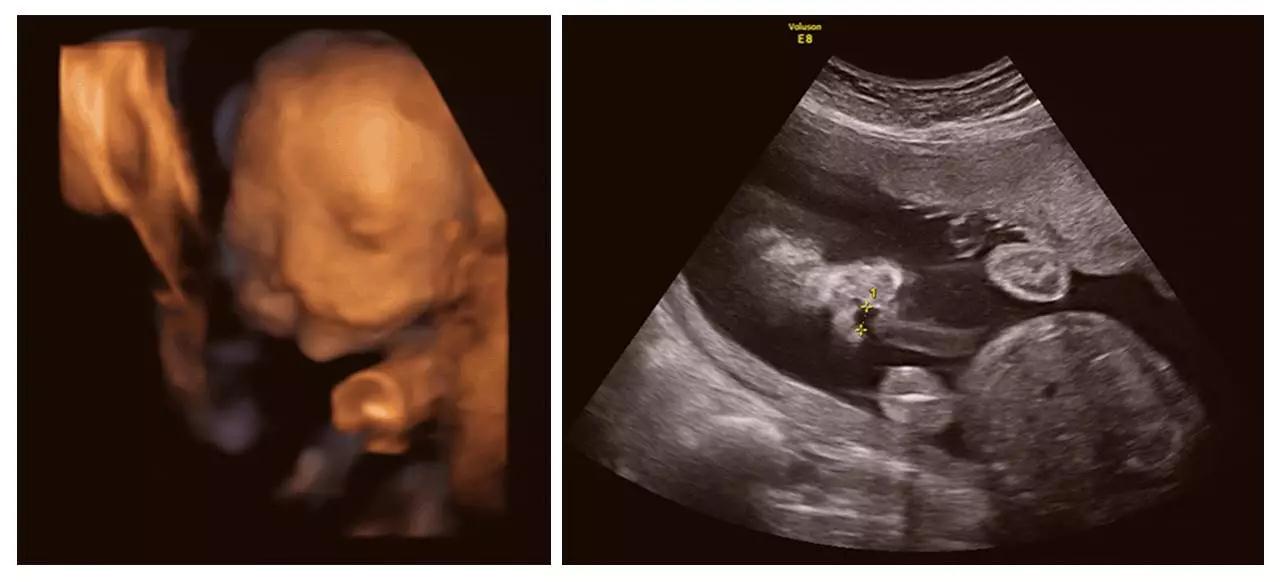

近日,美对宝宝在妈妈子宫里相拥亲吻的照片在网络疯传。据报道,美准妈妈Carissa Gill非常期待自己双胞胎女儿们的到来,所以对她们的四维照片特别着迷,而近次孕检,让她有更为惊喜的发现。

在Carissa怀孕25周的次孕检中,她在四维彩超(四维彩超)视频中发现,自己的个女儿首先亲吻了另个女儿的胸口,然后她们慢慢接近,后竟然相互用嘴亲吻!

夫妇俩给两个女儿取名为Isabella和Callie。妈妈Carissa把图像照片上传到了社交网站上。她在其中张照片中写道,Isabella在姐姐Callie的脸颊上印了个吻。在另张照片中,她写道,在这刻她很感恩,迫不及待地想要认识这两位珍贵的公主。

正是通过神奇的四维彩超(四维彩超),我们起见证了这有爱的幕。四维彩超(四维彩超)的出现对于妇产科学界意义重大,在探头下,我们可以清晰地看见宝宝的动态,看见宝宝发育的情况。不仅如此,四维彩超(四维彩超)能通过清晰的画面对胎儿的体表进行检查,及早发现唇裂、脊柱裂,大脑、肾、心脏、骨骼发育不良等各种畸形情况,检测和发现各种异常。简单的说,四维彩超(四维彩超)的作用,就是从零岁起监测宝宝的发育情况,保障每个新生儿的健康!

济南艾玛妇产医院作为山东首家 JCI 金牌妇产专科医院,在今年年初,又顺利成为济南市基本医疗保险定点医疗单位,集医疗安全和客户就诊的便捷度于体。济南艾玛妇产医院直非常重视围产期保健及宝宝出生缺陷的预防,率先引进美GE-E8高清四维彩超(四维彩超)设备,从0岁开始守护宝宝的健康,见证宝宝的成长。